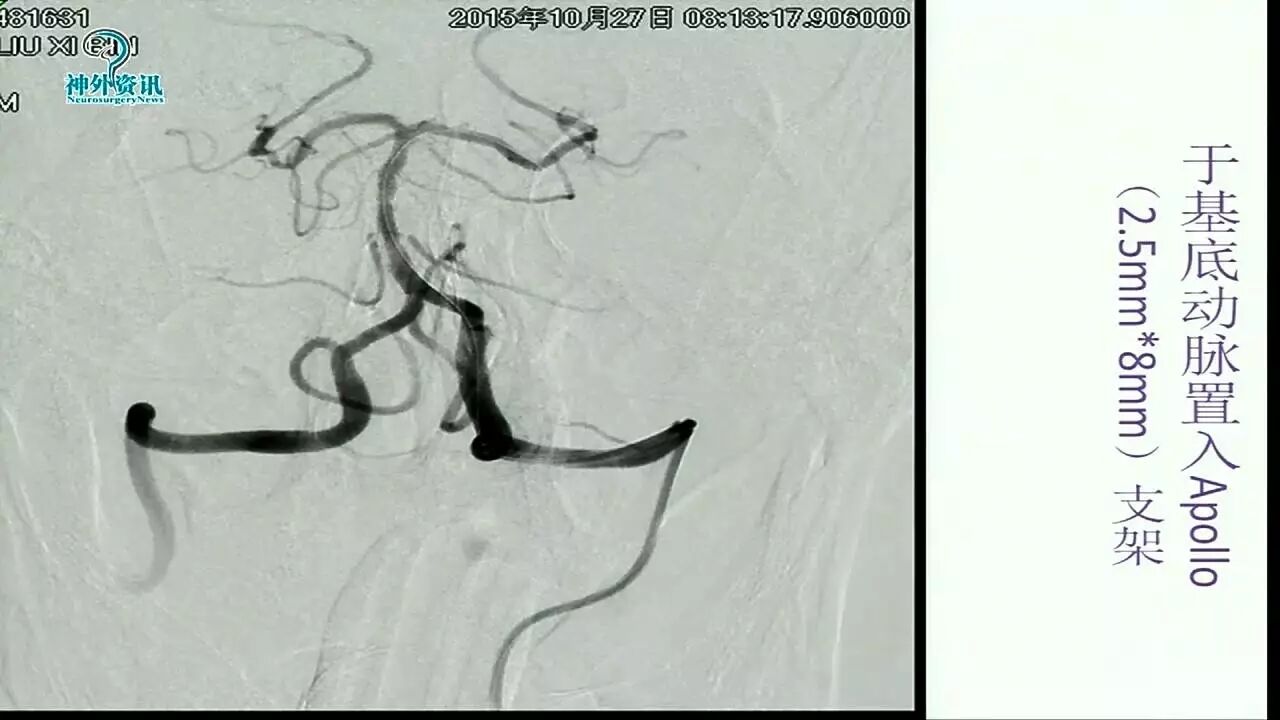

Enterprise支架在缺血性脑血管病中的应用